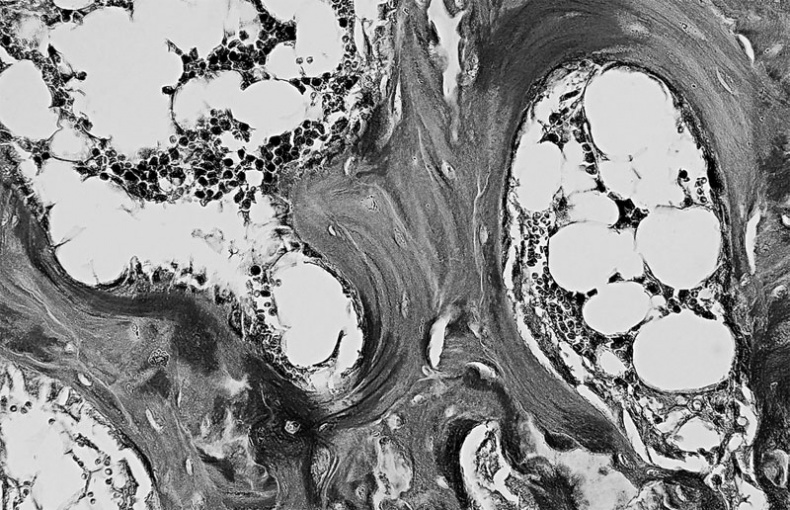

Особенность третья — костная ткань имеет пластинчатое строение. Каждая пластинка представляет собой тонкий пучок параллельно расположенных коллагеновых волокон, между которыми находятся остеоциты и аморфное вещество, содержащее кристаллы минеральных солей. Волокна соседних пластинок располагаются под углом друг к другу, часть их переходит из одной пластинки в другую, что обуславливает их плотное соединение, а, следовательно, и высокую прочность костей. Пластинок, располагаются вокруг каналов, в которых проходят кровеносные сосуды и нервы, образуя многослойные концентрические цилиндры.

Костные пластинки, образующие канал для кровеносного сосуда (в центре)

Иллюстрация к книге — Анатомия на пальцах [_46.jpg]